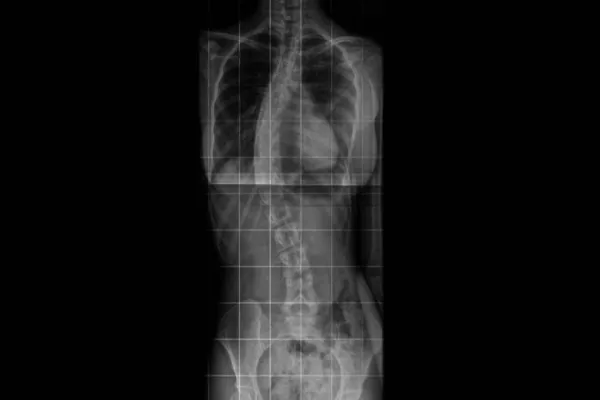

Ana Carolina de Oliveira dos Santos é moradora de Cascavel está precisando de ajuda para uma cirurgia para correção da escoliose idiopática

A jovem descobriu a doença no final de 2019, a escoliose idiopática está com uma curvatura de 46 graus e meio, tem avançado e ela precisa com urgência de uma cirurgia de correção e não tem como custear o tratamento.

Chegando em SJP em Janeiro de 2020 eu fui no UPA Cajuru tirar um raio x da minha coluna, e ali meu mundo desabou...Descobri que estava com escoliose idiopática com uma curvatura de 45° graus, isso é um problema que ocorre desde o nascimento mas apareceu em mim com o tempo por conta de carregar mochila pesada, postura incorreta, por conta disso foi piorando, quando eu descobri eu chorava desesperada escondido pra minha mãe não ficar mais preocupada do que ela já estava, foram noites de choro se perguntando porque aquilo tava acontecendo comigo. Passei por ortopedistas que disseram que meu caso era só cirúrgico, fiz fisioterapia e não adiantou, vim embora para Cascavel no final de 2020 e aqui fiz outro raio x, procurei um ortopedista pra ele examinar o raio x e ele disse que meu grau vai aumentar 1° por ano (estou com 46° graus e meio atualmente), e que isso poderia botar em risco meu coração e pulmão por conta da curvatura empurrar ambos, podendo me trazer vários riscos quando eu fizer 20 anos de idade (como infarto, por conta do coração inchar tentando pulsar o sangue para o corpo), e não é nenhum drama gente eu sinto dor nas costas em tempo de chuva de frio, tem vezes que imploro pra minha mãe me levar no upa pra tomar alguma injeção pra amenizar, se eu andar demais minha perna direita trava e eu não consigo andar, eu não tô ligando pra questão de estética pra deixar meu corpo normal como de qualquer outra pessoa, eu só tenho medo de piorar essas dores?